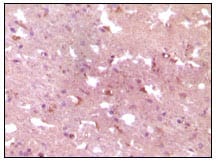

分类: 科研抗体货号: 20069别名: APP应用: IHC反应种属: Human